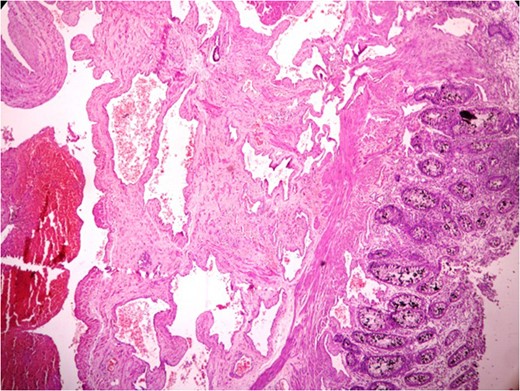

Thickened wall with tiny cystic spaces in mucosa, muscularis propria and serosa of the wall (inset: histopathological picture of the same area).

Histopathologically diagnosis of Cavernous Vascular Malformation—Diffuse infiltrating (expansive) type was given.